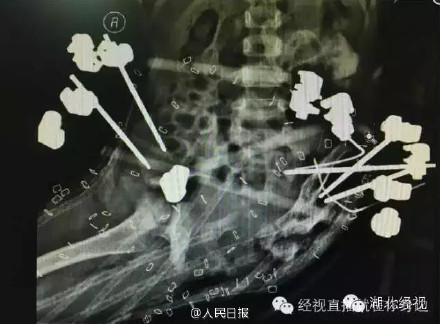

武汉协和医院小儿骨科专家李进副教授介绍,在外科,像小思语这种“半骨盆离断伤”是所有可救治创伤中最重的,绝大多数患者 均当场死亡,连救治机会都没有。在国内外有人类医学文献记录以来,世界上能够存活下来的人不到50个,仅4岁的小思语是年龄最小的一个。 为救活她,协和医院举行了全院专家会诊,按照最佳的治疗方案,小思语要想康复,需要皮肤能够覆盖住裸露在外的肠道等内脏器官,预计需要两个月左右的治疗时 间以及上十次的手术。 目前小思语坏死的肌肉和骨组织等已经基本清理完毕,开始生长出新鲜的肉芽。但是她左下半身的肌肉无法新生,肠道等盆腔内器官组织仅有一层腹膜包住,如果座起或者直立下身就会往下脱出,目前只能用人工皮覆盖兜住,通过吸引排除代谢的废物。人工皮与真正的皮肤组织不同,不能够终生维持,7天左右就会堵住,代谢的组织积聚会引起感染,每更换一次价格不菲。协和医院的专家们会诊后,决定采用皮肤 牵张术,以每天1-2毫米的速度,将小思语上腹部和背部残留的皮肤缓慢向下牵拉,预计经过2个月左右的时间,争取能够覆盖住裸露在外的内脏器官并关闭伤口。如果顺利,随着小思语逐渐长大,再设法为她重建排便和泌尿系统、并通过人工骨盆争取站立,甚至在青春期后重建生育功能。